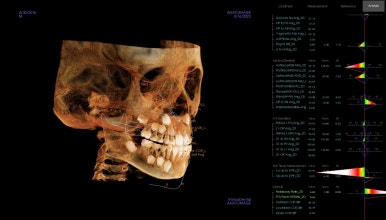

다양한 골격분석 뿐만 아니라 호흡기 구조까지 살펴보게 되는데요.

골격의 주걱턱 패턴이 심하지 않은데, 앞니가 반대교합인 경우는 반드시 호흡문제를 함께 봐야 됩니다.

원인을 알아야 치료 후에도 그 결과가 잘 유지될 수 있거든요.

이번 환자분도 호흡기 문제에 기인한 혀의 위치 불량으로 아래 앞니가 자꾸 밀려나는 상태였습니다.